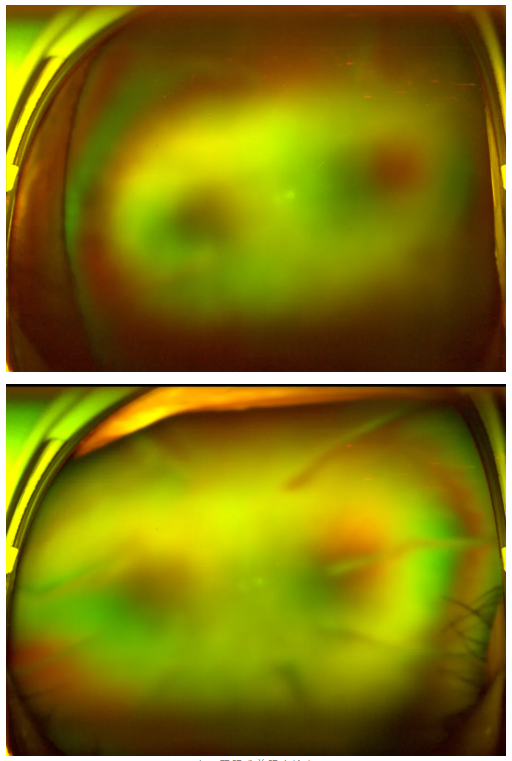

老王雙眼術(shù)前眼底檢查

“別灰心,好好配合治療,你還是有很大機(jī)會(huì)能恢復(fù)部分視力的。”王曉波主任的話像一顆定心丸,讓老王懸著的心得以放松。在醫(yī)生的指導(dǎo)下,老王先積極穩(wěn)定血糖,為后續(xù)治療打下堅(jiān)實(shí)基礎(chǔ),隨后多次轉(zhuǎn)機(jī)重返廈門(mén)眼科中心辦理入院,準(zhǔn)備接受針對(duì)性治療。

王曉波主任告知老王:術(shù)后復(fù)查眼底顯示,其糖尿病視網(wǎng)膜病變并不嚴(yán)重,因此視力得以得到明顯改善與提升。當(dāng)初堅(jiān)持治療、不輕言放棄,是非常正確的選擇!

術(shù)后半個(gè)月復(fù)查時(shí),視力恢復(fù)情況更是喜人:左眼矯正視力達(dá)到1.0,右眼也恢復(fù)到0.8,不僅能清晰看清事物,甚至能正常閱讀、看電視,基本恢復(fù)了正常生活。

糖尿病視網(wǎng)膜病變